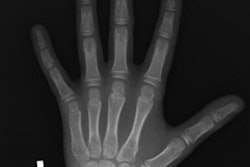

Called ensemble learning, the technique is designed to combine the best aspects of multiple machine learning algorithms into a single model to perform a task, such as identifying suspicious lung lesions or estimating bone age based on skeletal x-rays. Ensemble learning works best when each of the models performs well in their own right and correlation between the predictions of each model is relatively low.

They then used combinations of up to 10 algorithms at a time that were trained on a dataset of over 12,000 pediatric hand x-rays in which radiologists had determined true bone age. Then, the ensemble combinations were used to analyze 200 x-rays, with the combined model producing a mean absolute deviation (MAD) of bone age, with higher deviation indicating less accuracy.